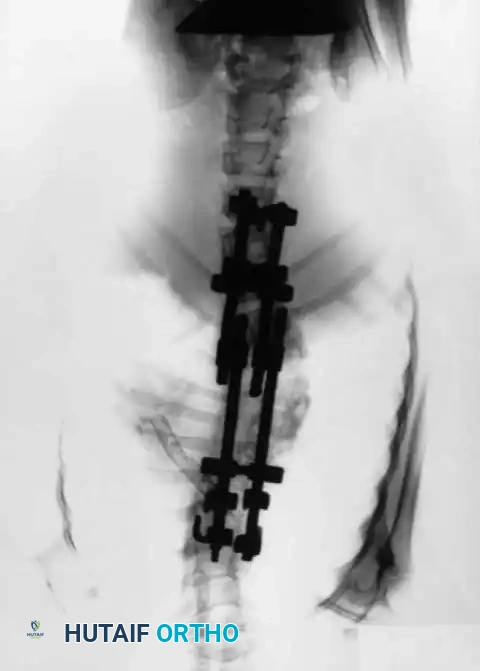

Fig. 23: Radiographic confirmation of segmental pedicle screw instrumentation.